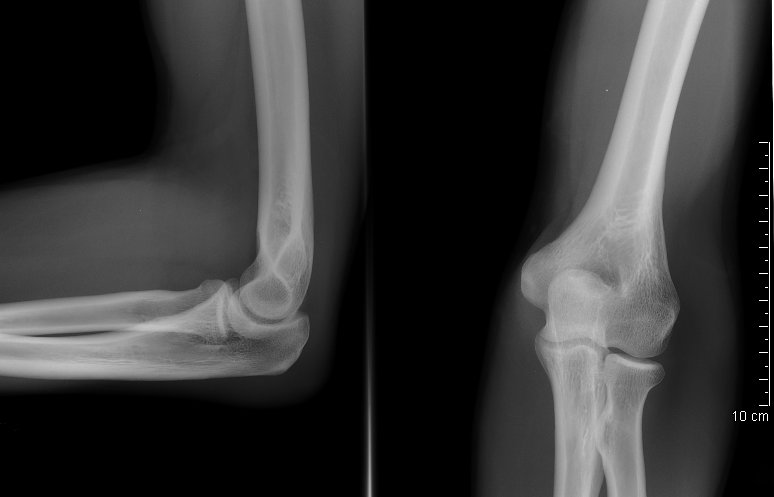

הדמיית רנטגן של מרפק במנח פשיטה (מימין) ובזווית של 90 מעלות כיפוף (משמאל). בתמונה הימנית נראים בבירור המרווח המפרקי של מפרק הזרוע והחישור וכן זווית הנשיאה של המרפק.